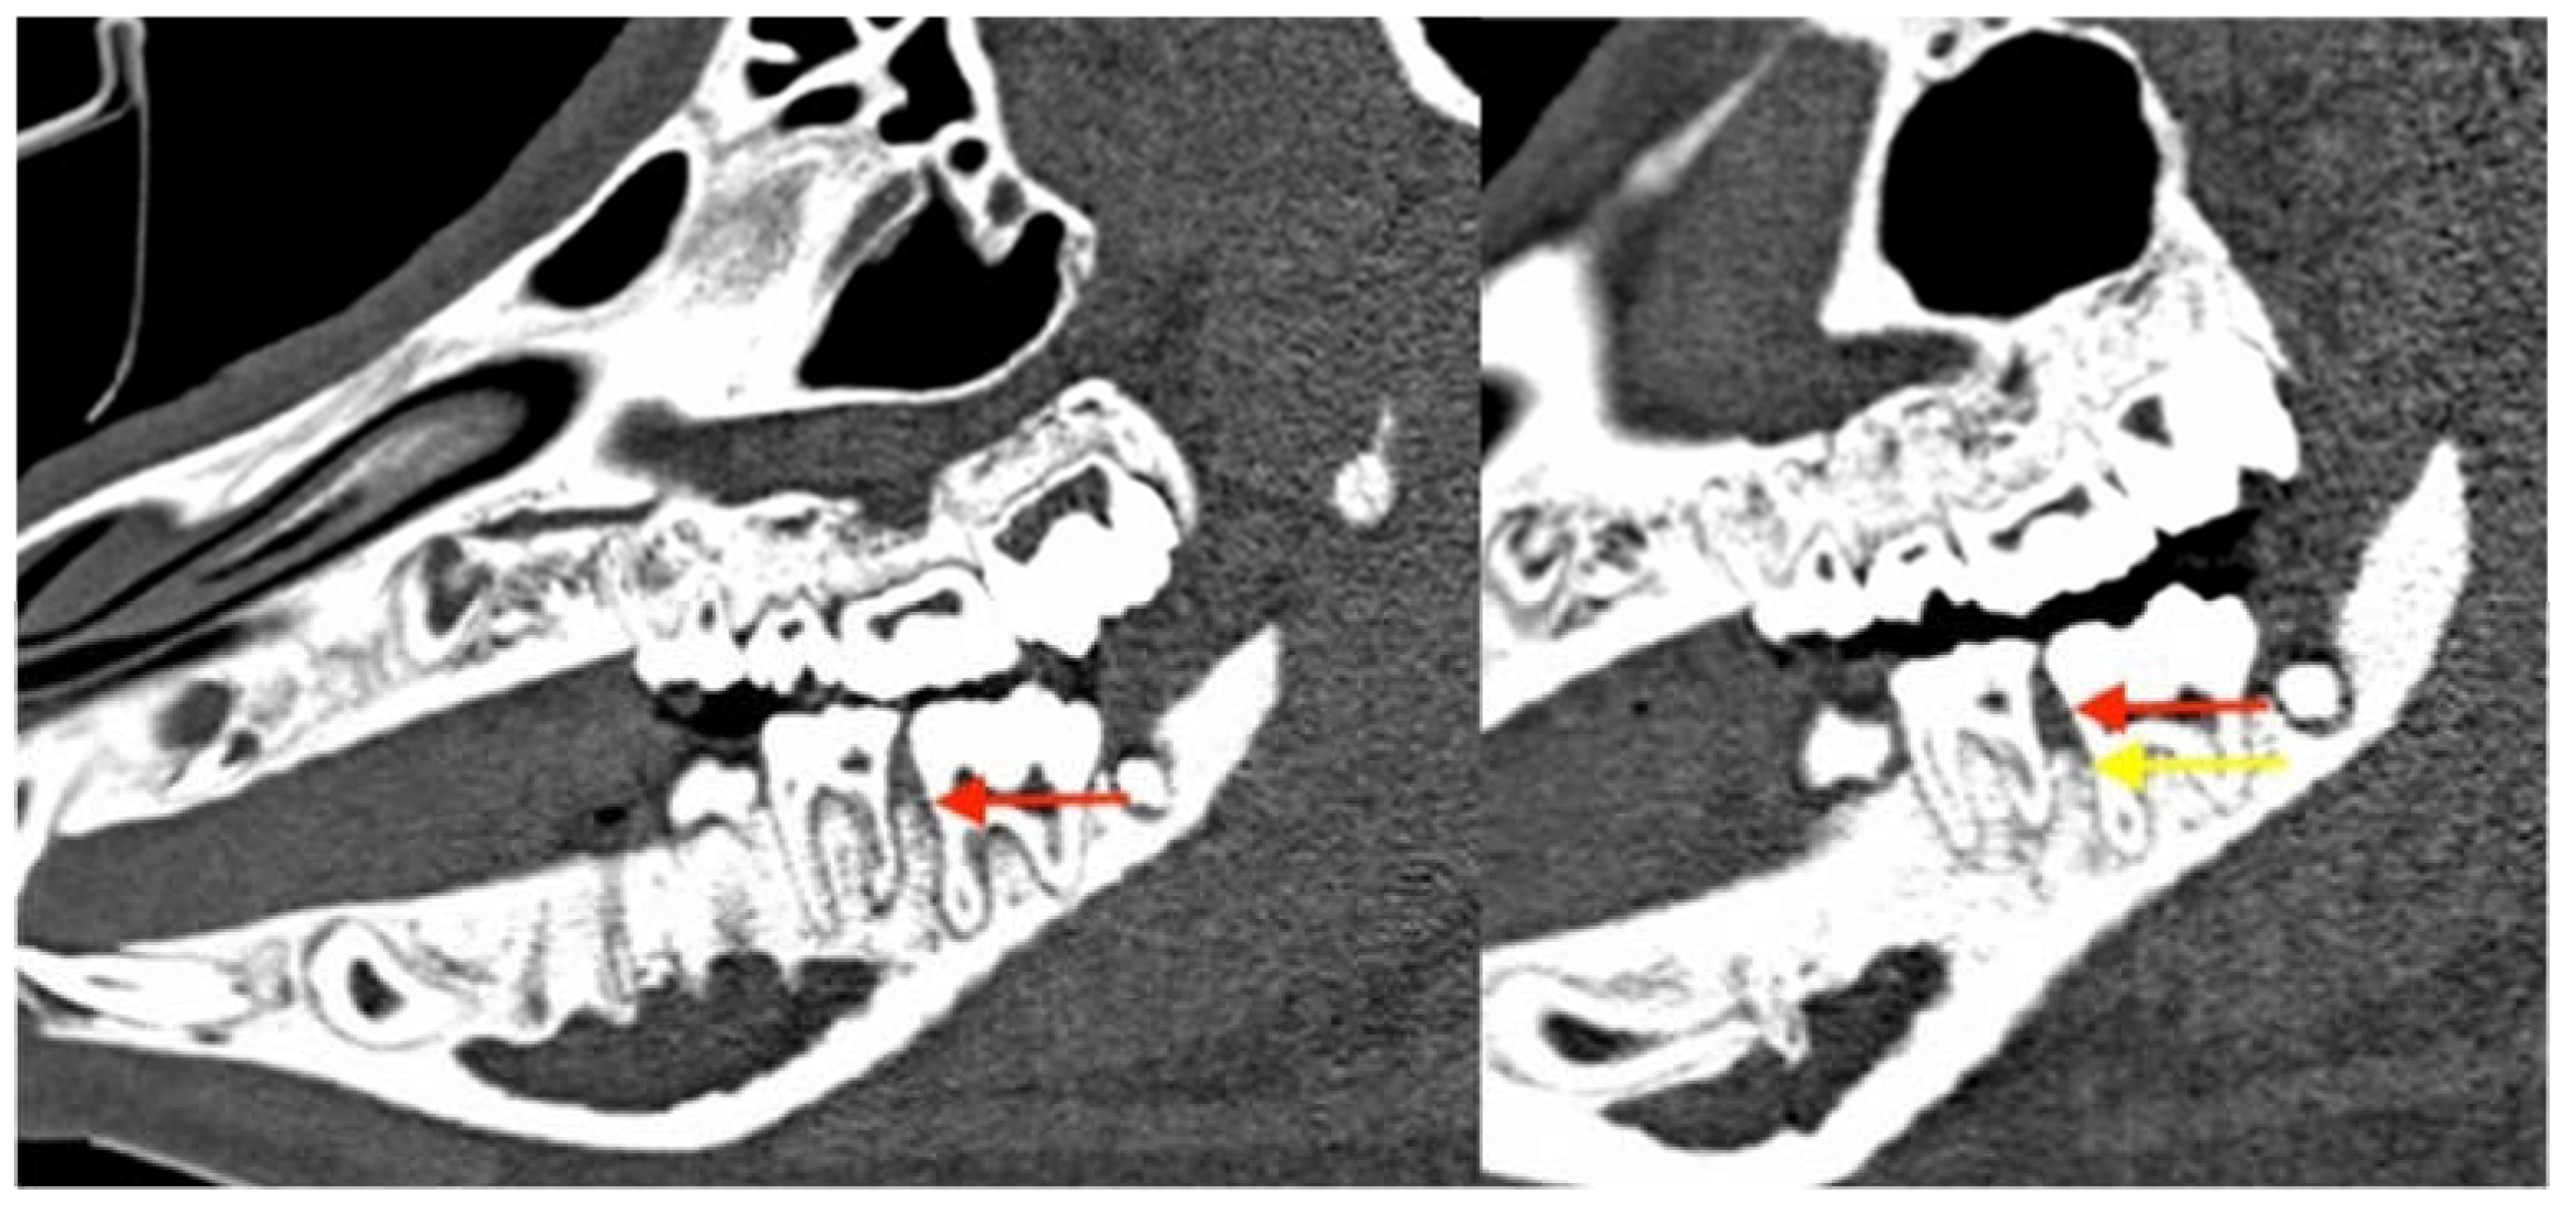

3.2.3. Radiological Evaluation